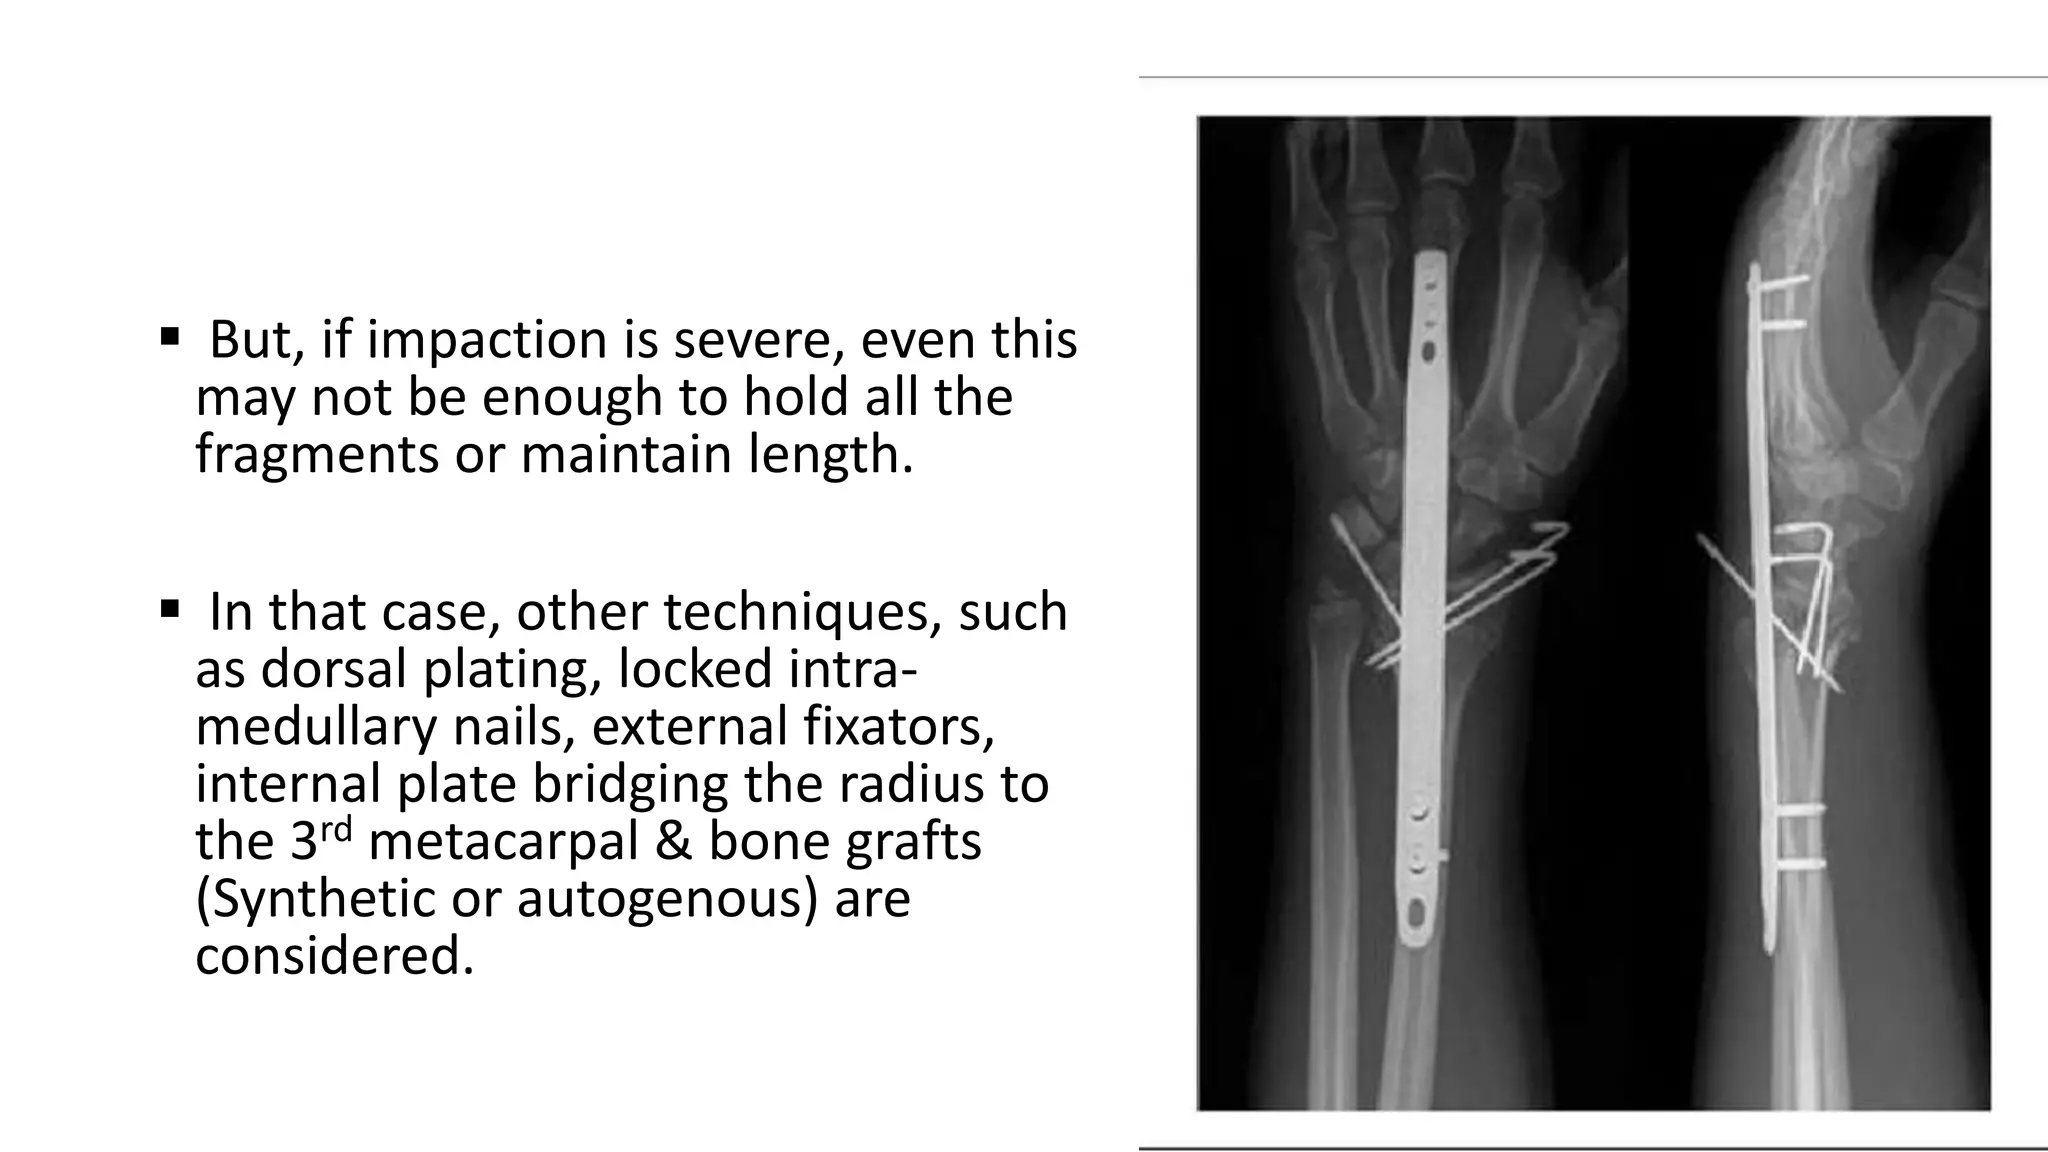

 But, if impaction is severe, even this

may not be enough to hold all the

fragments or maintain length.

 In that case, other techniques, such

as dorsal plating, locked intra-

medullary nails, external fixators,

internal plate bridging the radius to

the 3rd metacarpal & bone grafts

(Synthetic or autogenous) are

considered.